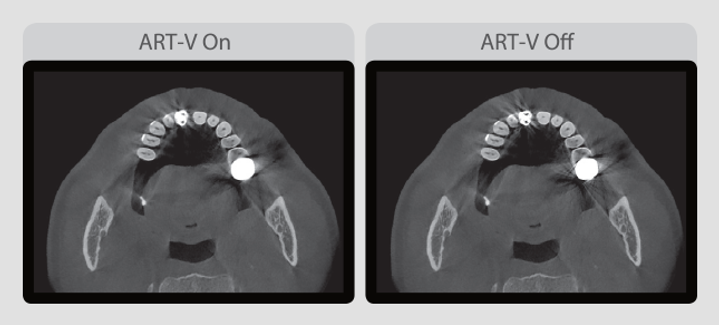

THE ART-V

Los artefactos metálicos dificultan la visualización y, naturalmente, reducen la confianza en el diagnóstico. Una imagen clara proporciona más seguridad para realizar un diagnóstico preciso, así la planificación de implantes y la creación de una guía quirúrgica es más eficiente.

*ART-V ES EL NUEVO NOMBRE DE LA FUNCIÓN MAR (TECNOLOGÍA DE REDUCCIÓN DE ARTEFACTOS) DE VATECH